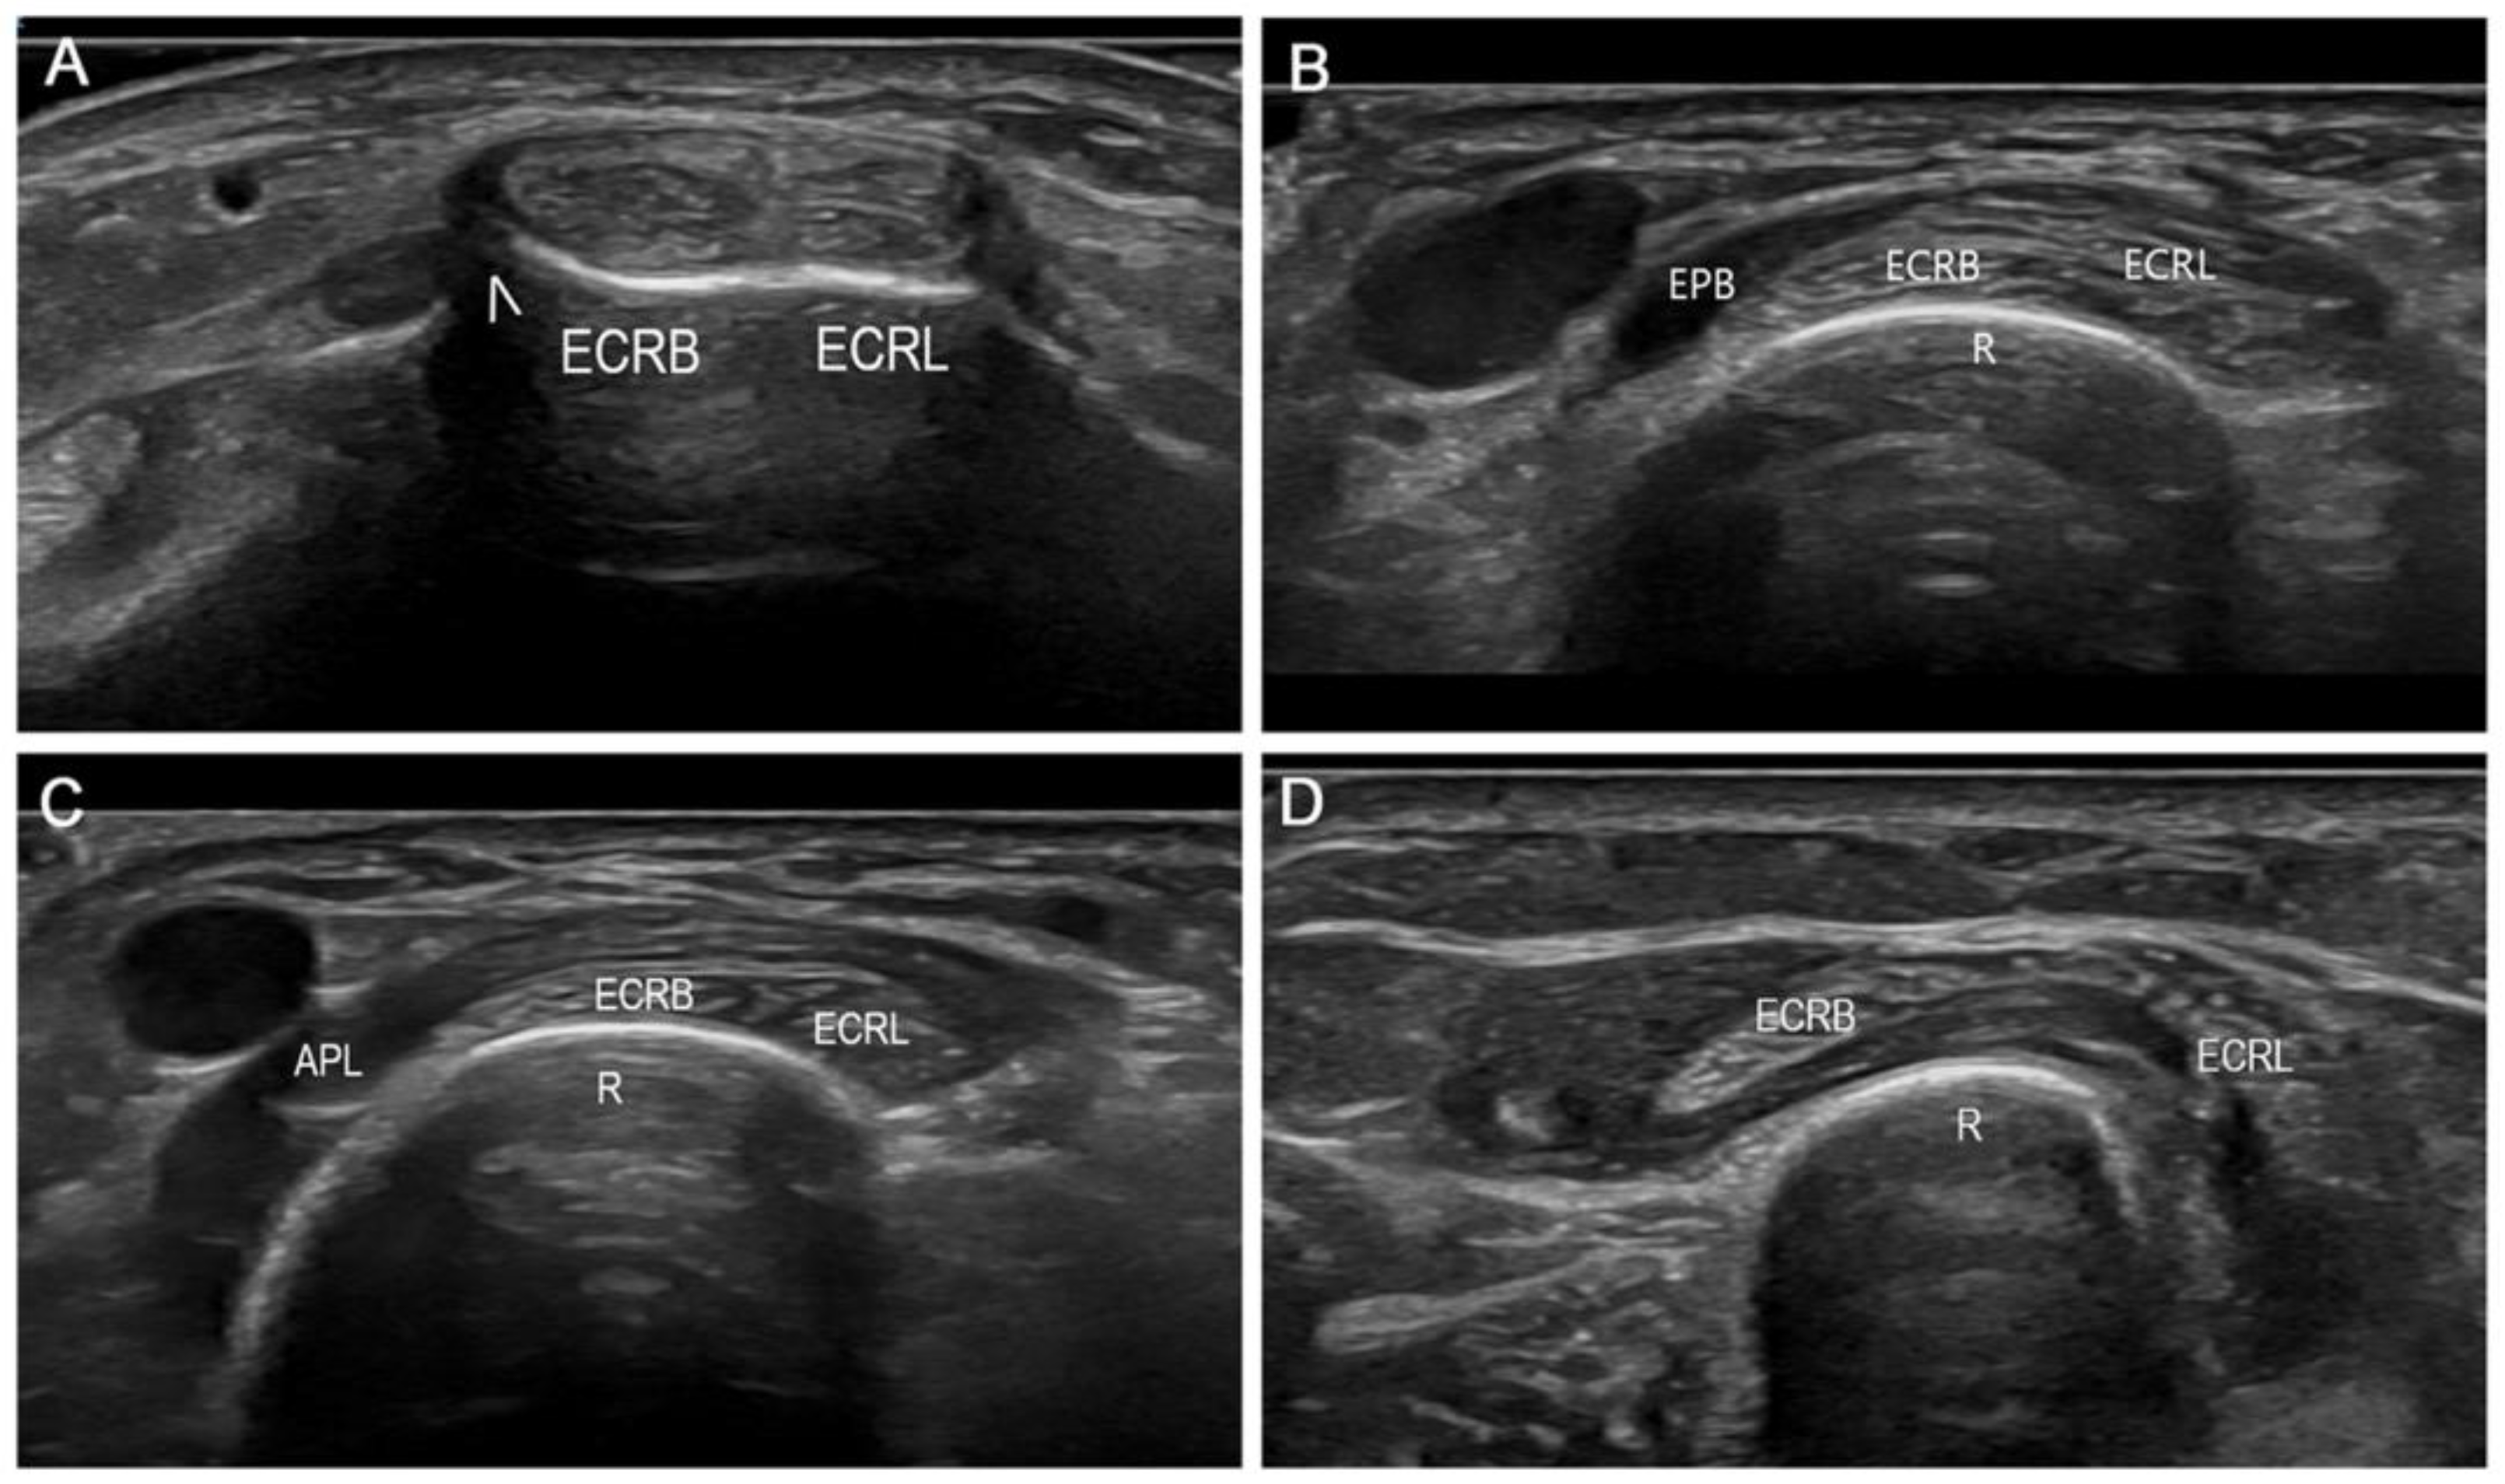

| Overexercise (i.e., rowing); crossing of APL and EPB on ECRB and ECRL | Excessive lifting with thumb up (i.e., newborn baby) | Perineural adhesions or neuroma (i.e., following the release of de Quervain disease) | Pressure from a bracelet, wristwatch, or handcuff | Cartilage degradation and bone overgrowth | Overexercise (i.e., drum player); crossing of EPL on E and ECRL |